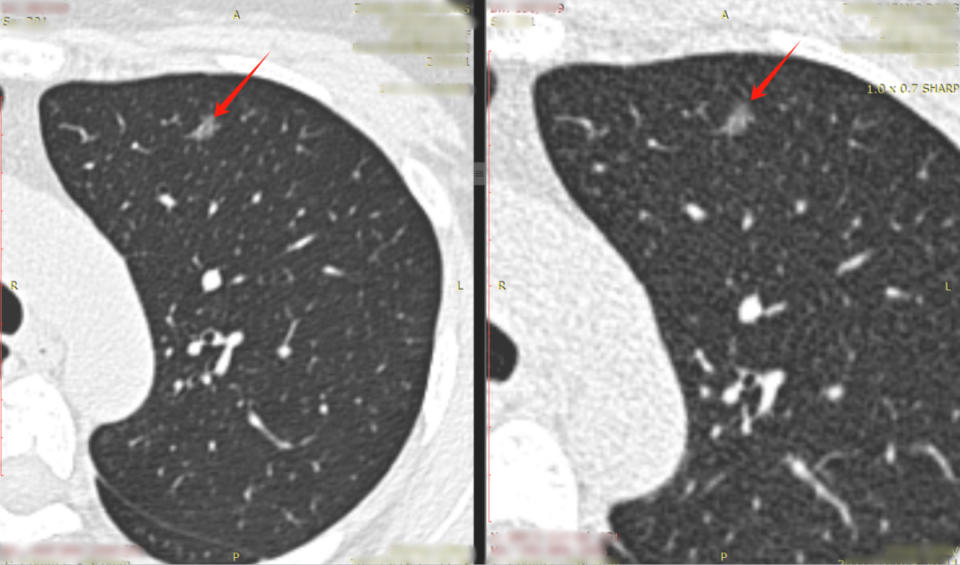

肺结节是指肺部出现的直径小于或等于3cm的圆形或类圆形病灶,虽然大多数肺结节是良性的,但部分可能是肺癌的早期表现,对肺结节的准确诊断和治疗具有重要意义,目前,随着低剂量计算机断层扫描(LDCT)的广泛应用,肺结节的检出率显著提高。